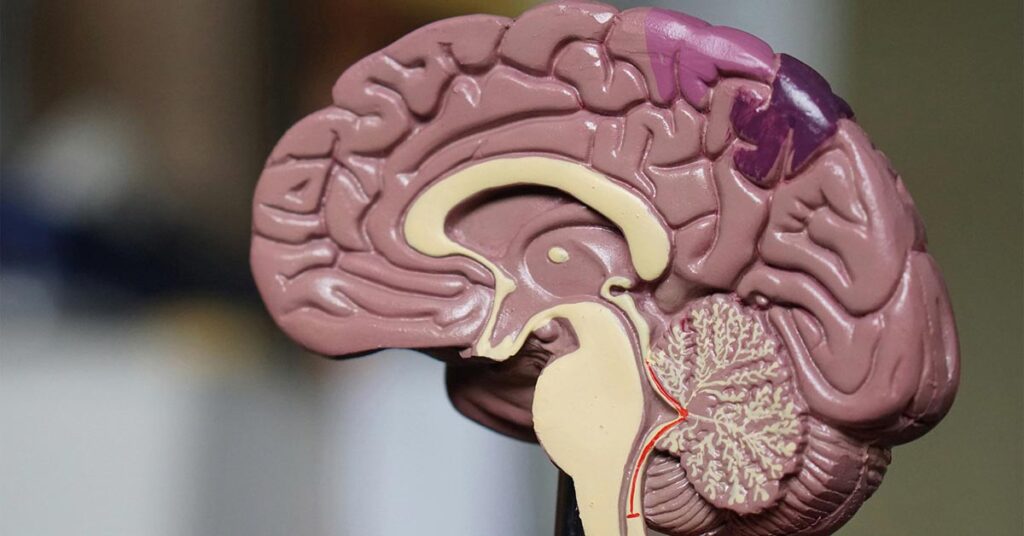

Científicos estadounidenses han identificado una prometedora alternativa para tratar el Alzheimer: fortalecer las defensas naturales del cerebro, en lugar de solo eliminar las placas tóxicas que caracterizan esta enfermedad.

El Alzheimer no es una consecuencia normal del envejecimiento, sino el resultado de procesos complejos que causan pérdida de neuronas años antes de que aparezcan los síntomas. Se asocia con el depósito anormal de proteínas beta amiloide y tau en el cerebro. Durante décadas, los tratamientos se han centrado en eliminar estas placas con fármacos, aunque con resultados limitados.

Un estudio reciente de Northwestern University plantea un enfoque diferente: activar las células inmunitarias del cerebro, llamadas microglías, para que eliminen las placas de manera más eficaz y sin provocar inflamación, como sucedió en intentos previos de inmunización.

Microglías: el equipo de limpieza cerebral

Gracias a una técnica de vanguardia llamada transcriptómica espacial, los investigadores analizaron cerebros de personas fallecidas con Alzheimer, algunas de las cuales habían recibido tratamientos experimentales. Descubrieron que cuando los fármacos funcionan, las microglías no solo eliminan las placas, sino que ayudan a restaurar el equilibrio cerebral.

Este estudio reveló que no todas las microglías reaccionan igual: algunas responden eficazmente al tratamiento y otras no. Además, ciertos genes se activan en las microglías de los pacientes que responden mejor, lo que podría abrir la puerta a terapias más personalizadas en el futuro.

Un equipo de la Universidad Northwestern (UN) comprobó que las células inmunitarias del cerebro eliminan las placas de la proteína tóxica beta amiloide asociadas a la enfermedad de Alzheimer, y restauran un entorno cerebral más saludable.

Detener la cascada amiloide

El estudio también respalda la teoría de la “cascada amiloide”: si las placas se eliminan a tiempo, podrían evitarse daños mayores, como la aparición de la proteína tau, responsable del deterioro cognitivo. Esto sugiere que aplicar estos tratamientos en etapas tempranas podría cambiar el curso de la enfermedad.

Un futuro más esperanzador

Aunque todavía no existe una forma de dirigir los medicamentos específicamente a las microglías, los investigadores confían en que entender mejor su funcionamiento y genética permitirá desarrollar tratamientos más eficaces. “Si podemos activar las células correctas sin fármacos invasivos, podríamos cambiar la historia del Alzheimer”, afirma el investigador David Gate.

Este estudio, basado en 25 cerebros post mortem, representa un avance clave en la búsqueda de terapias que aprovechen el potencial natural del propio cuerpo para combatir esta devastadora enfermedad.